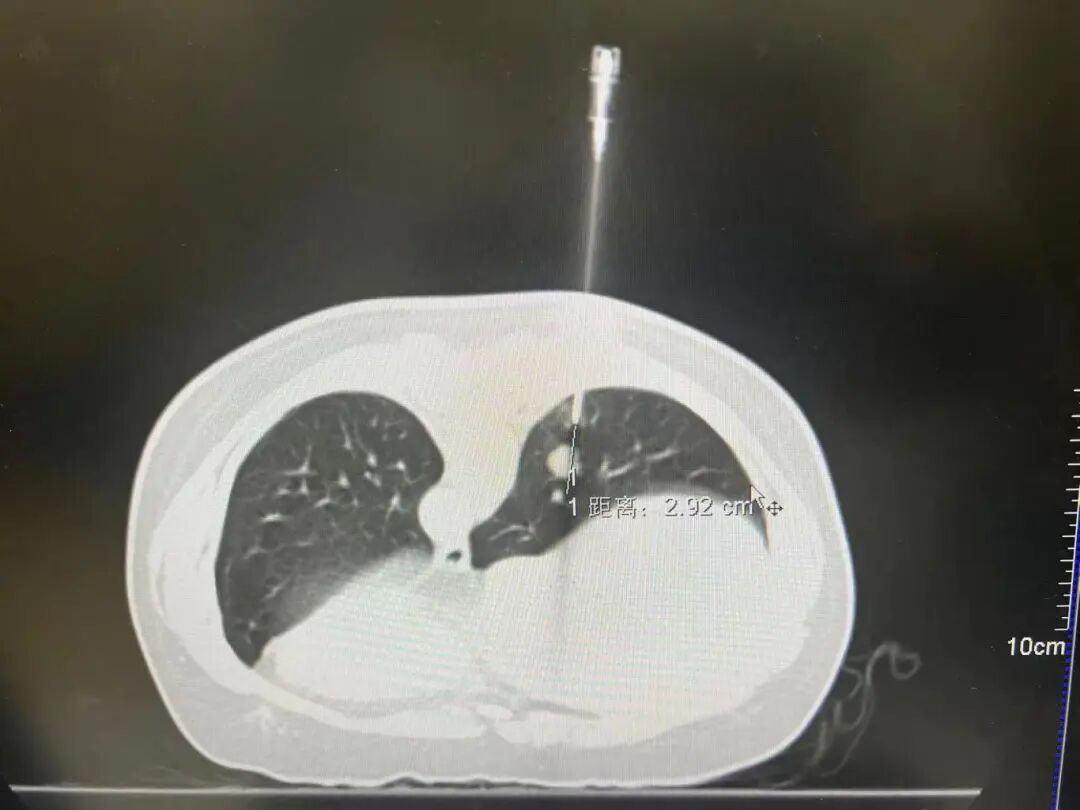

在肿瘤三区主任卢奕宇的带领下,成功运用“同轴针穿刺+明胶海绵封堵技术”,为李顺利进行了病理活检。过程中,李几乎没感受到什么痛苦,活检就已经完成了。

卢奕宇主任在CT下运用同轴针穿刺+明胶海绵封堵技术为患者进行病理活检。

• 同轴针穿刺技术是指先用同轴定位针穿刺至目标病变组织附近,拔出针芯后,活检针顺着同轴针鞘进针,对病变组织进行活检。